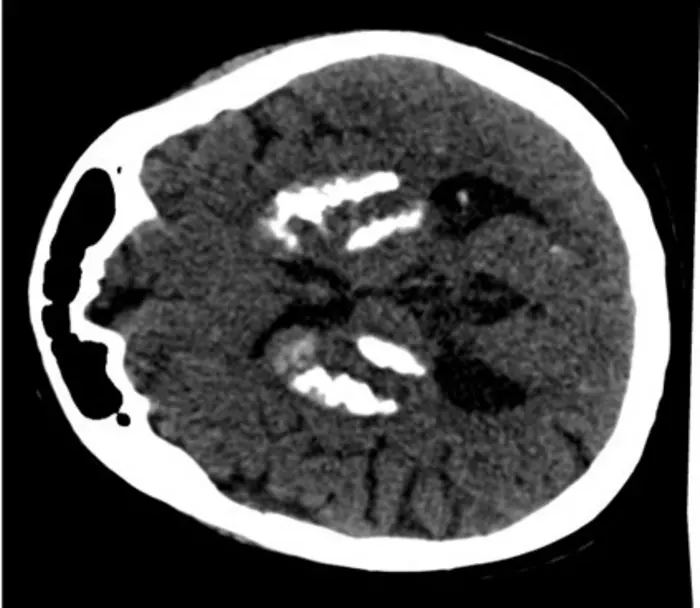

Peer-Reviewed PublicationIMAGE:

CT SCAN OF A PATIENT WITH BRAIN CALCIFICATION. PHOTO: VIORICA CHELBAN

Brain calcification can cause movement disorders and cognitive impairment. Researchers at the Arnesen Lab at UiB have now identified a gene that provides new insight into how these calcifications occur.

She and several others in the Arnesen lab have taken a closer look at a specific type of brain calcification, called primary familial brain calcification (PFBC, formerly called Fahr's disease). In this rare neurodegenerative condition, progressive muscular symptoms, psychiatric symptoms and cognitive impairment occur:

"This condition is caused by pathogenic, meaning disease-causing, gene variants and entail particularly severe brain calcification", says Aksnes.